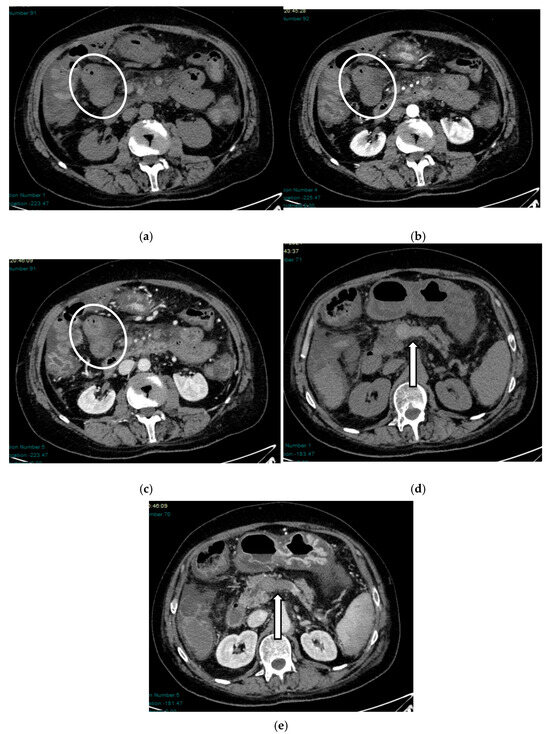

Acute mesenteric ischemia (AMI) is a clinical condition caused by vascular insufficiency, resulting in intestinal damage. Is often underestimated, if not driven by clinical suspicion, due to the non-specific clinical symptoms (usually represented by acute abdominal pain) and the absence of reliable markers, which results in a poor prognosis and high mortality. We can identify three main forms of AMI: arterial, venous, and non-occlusive. Arterial AMI is the most frequent form, caused by occlusion of the superior mesenteric artery or one of its branches. Venous AMI is the least frequent, caused by thrombosis of the superior mesenteric vein or its branches. Non-occlusive AMI is due to a state of hypovolemia, which is frequent in patients who have undergone surgery. Given the difficulty of diagnosis based on the clinic alone, the radiologist plays a central role in identifying radiological signs of intestinal ischemia and in avoiding misdiagnosis. The radiologist’s role is mainly to identify factors predictive of necrosis, which allow us to stratify patients and direct them towards the proper management. The aim of this review is to provide indications for an adequate CT protocol, including an unenhanced phase, an arterial phase, and a venous phase, as well as to underline the features to investigate in the different forms of AMI, in order to increase the diagnostic capacity in this challenging disease. Full article

Figure 1